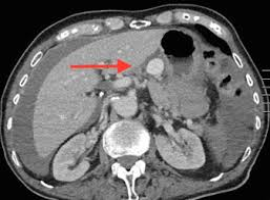

Citation: Louise Dunphy, Syed Hussain Abbas, Gisella Salerno, et al. Endovascular Management of a Gastric Artery Aneurysm Rupture. Clin Image Case Rep J. 2019; 1(2): 106.